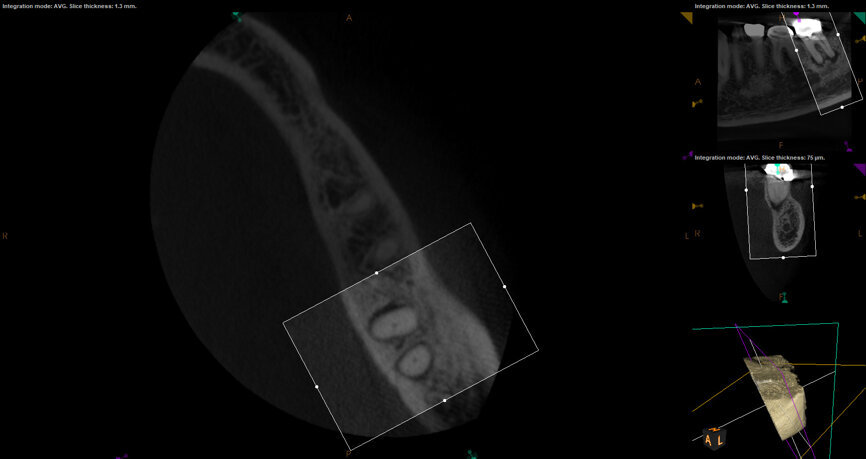

Fig. 17a: Case assisted with CBCT to determine anatomy pre-operatively. Note the multiple cross sections moving apically and the correlation to the 2-D view. Note also the conservative taper in relation to the root width. (Courtesy of Dr. Brett Gilbert)

Fig. 17b: Case assisted with CBCT to determine anatomy pre-operatively. Note the multiple cross sections moving apically and the correlation to the 2-D view. Note also the conservative taper in relation to the root width. (Courtesy of Dr. Brett Gilbert)

Fig. 17c: Case assisted with CBCT to determine anatomy pre-operatively. Note the multiple cross sections moving apically and the correlation to the 2-D view. Note also the conservative taper in relation to the root width. (Courtesy of Dr. Brett Gilbert)

Fig. 17d: Case assisted with CBCT to determine anatomy pre-operatively. Note the multiple cross sections moving apically and the correlation to the 2-D view. Note also the conservative taper in relation to the root width. (Courtesy of Dr. Brett Gilbert)

Fig. 17e: Case assisted with CBCT to determine anatomy pre-operatively. Note the multiple cross sections moving apically and the correlation to the 2-D view. Note also the conservative taper in relation to the root width. (Courtesy of Dr. Brett Gilbert)

Fig. 17f: Case assisted with CBCT to determine anatomy pre-operatively. Note the multiple cross sections moving apically and the correlation to the 2-D view. Note also the conservative taper in relation to the root width. (Courtesy of Dr. Brett Gilbert)

Managing complex anatomy is much simpler if the clinician has a pre-operative road map. The CBCT provides the roadmap and the surgical microscope the lens (literally) through which to visualize the result. Aside from a relaxed patient who is profoundly numb, being able to visualize anatomy by taking a pre-operative (and possibly intra-operative) CBCT and using a surgical microscope during treatment have no substitutes. They are the current “Gold Standard” in that 3-D imaging shows the clinician the true reality of a clinical situation as opposed to the suggestion gained from a 2-D radiograph. Proper interpretation of imaging prior to and/or during endodontic treatment goes a long way in taking the “guesswork” out of identifying canal location and other anatomical complexities as the procedure unfolds. In a 2014 study by El Fayad and Johnson, it was determined that when having a pre-operative CBCT as compared to 2-D radiographs alone, the treatment plan was modified 62 percent of the time. This is a huge game changer to think that the information learned from 3-D imaging changed the plan of treatment over six times out of 10 (Fig. 4).[2]